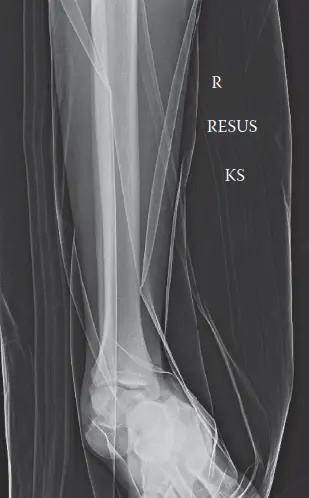

تُعد الأشعة السينية هي الخطوة الأولى والأساسية في تشخيص خلع تحت الكاحل. يتم التقاط صور متعددة للقدم والكاحل من زوايا مختلفة (أمامية خلفية، جانبية، ومائلة للقدم، وأمامية خلفية وجانبية للكاحل).

• المنظر الجانبي (Lateral View): يُظهر فقدانًا كاملًا للاتصال بين عظم الكاحل وعظم العقب، وبين عظم الكاحل والعظم الزورقي. يظل عظم الكاحل متوافقًا مع عظم الساق البعيد، مما يؤكد أنه خلع تحت الكاحل حقيقي. يظهر عظم العقب منزاحًا إلى الخارج والأمام بالنسبة لعظم الكاحل. ويُرى رأس عظم الكاحل منزاحًا إنسيًا (داخليًا) عن العظم الزورقي. هذا النمط يتوافق تمامًا مع خلع تحت الكاحل الإنسي .

• المنظر الأمامي الخلفي (AP View): يؤكد الإزاحة الإنسية لرأس عظم الكاحل عن العظم الزورقي. يظهر عظم العقب في وضع التقوس للخارج (Valgus) بالنسبة لعظم الكاحل.

• المنظر المائل (Oblique View): يوفر منظورًا إضافيًا لخلل المفصل الكاحلي الزورقي.

• صور الكاحل: تُظهر عدم وجود خلع متزامن في مفصل الكاحل العلوي (بين الساق وعظم الكاحل) أو كسور كبيرة في الكاحل.

صورة أشعة جانبية توضح خلعًا إنسيًا تحت الكاحل. لاحظ أن مفصل الساق والكاحل سليم، مع فقدان كامل للتراصف بين عظم الكاحل والعقب والزورقي.